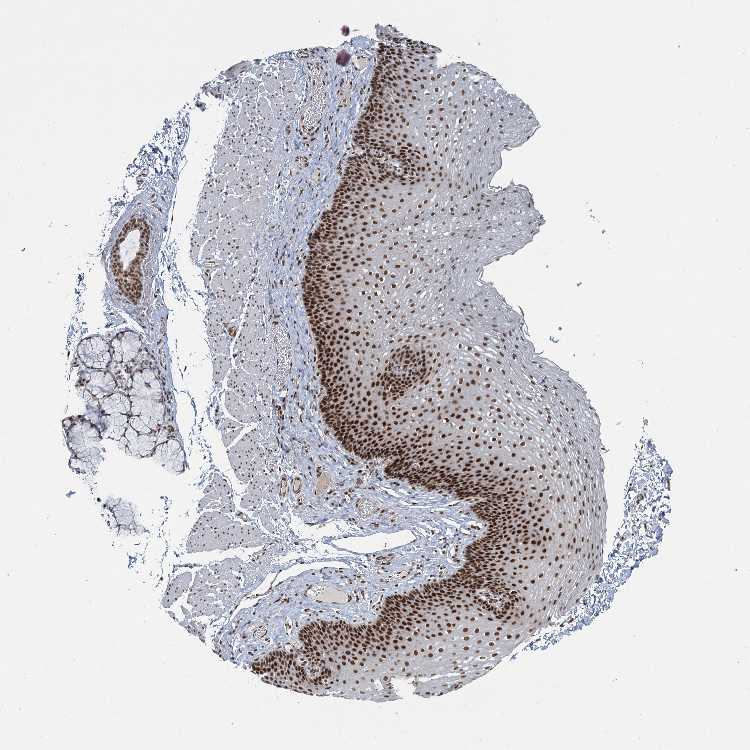

ESOPHAGUS - Antibody stainingi

Antibody staining in the annotated cell types in the current human tissue is reported as not detected, low, medium, or high, based on conventional immunohistochemistry profiling in selected tissues. This score is based on the combination of the staining intensity and fraction of stained cells.

Each image is clickable and will lead to virtual microscopy that enables deeper exploration of all samples and also displays staining intensity scores, fraction scores and subcellular localization as well as patient and tissue information for each sample.

Antibody HPA038902Antibody HPA038903

Squamous epithelial cells MediumHigh